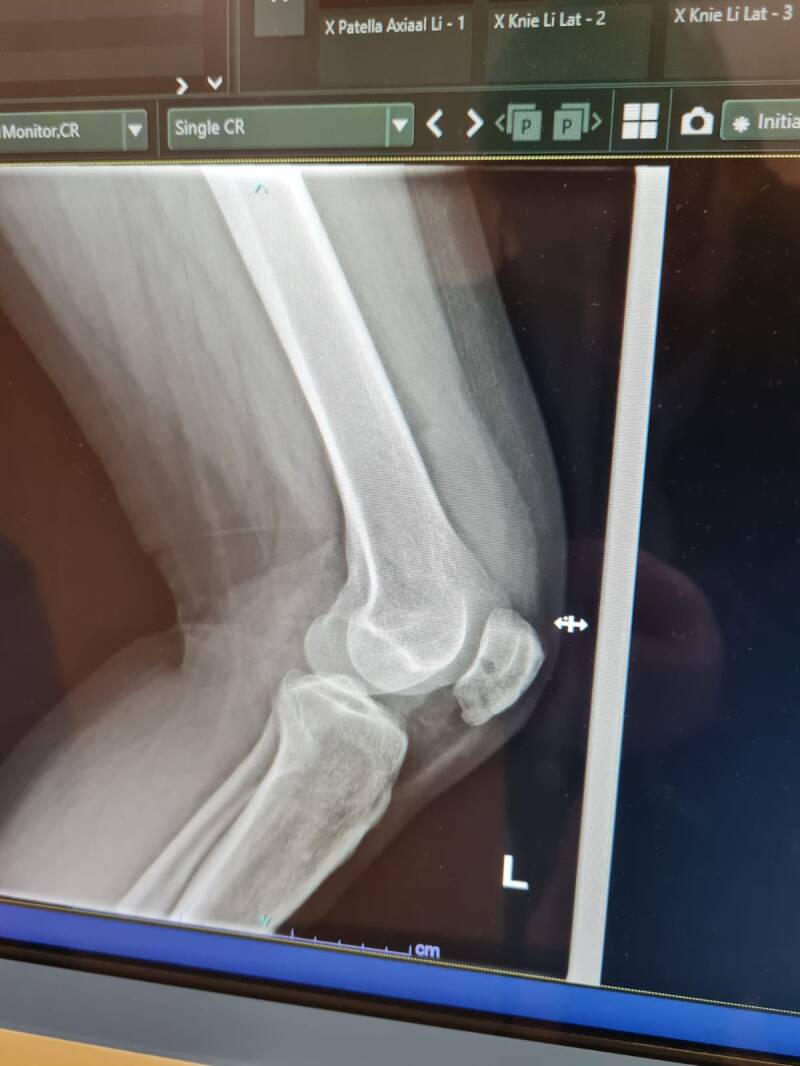

De rit naar het ziekenhuis was pijnlijk en gelukkig was er een rolstoel om mij naar de radiologie te rijden. Daar werden foto's gemaakt en ze vroegen of ik mijn been wilde strekken, maar dat ging niet. Ondanks dat was er duidelijk een breuk te zien, verticaal over mijn knieschijf. Ik mocht mij melden bij de gipskamer, dus ik strompelde met de krukken, die mijn man van huis had meegenomen naar de wachtruimte.